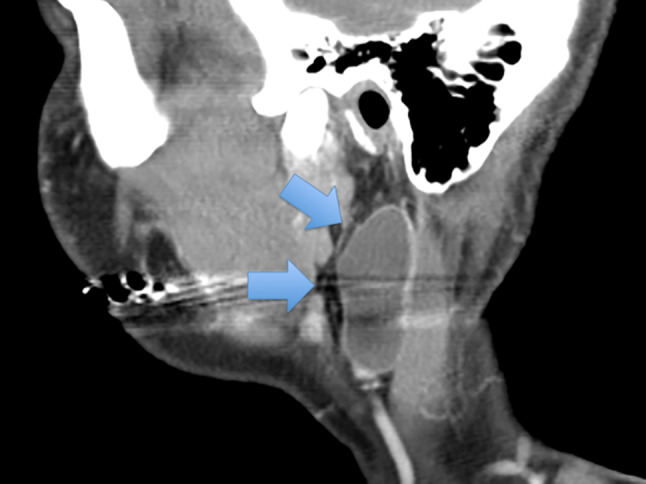

Fig. 6.

CT scan showing a lymphoepithelial cyst (arrows) within the parotid gland